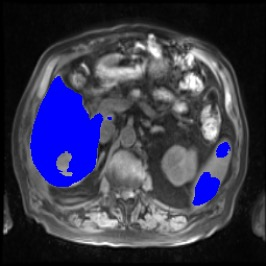

Integrating high-level semantically correlated contents and low-level anatomical features is of central importance in medical image segmentation. Towards this end, recent deep learning-based medical segmentation methods have shown great promise in better modeling such information. However, convolution operators for medical segmentation typically operate on regular grids, which inherently blur the high-frequency regions, i.e., boundary regions. In this work, we propose MORSE, a generic implicit neural rendering framework designed at an anatomical level to assist learning in medical image segmentation. Our method is motivated by the fact that implicit neural representation has been shown to be more effective in fitting complex signals and solving computer graphics problems than discrete grid-based representation. The core of our approach is to formulate medical image segmentation as a rendering problem in an end-to-end manner. Specifically, we continuously align the coarse segmentation prediction with the ambiguous coordinate-based point representations and aggregate these features to adaptively refine the boundary region. To parallelly optimize multi-scale pixel-level features, we leverage the idea from Mixture-of-Expert (MoE) to design and train our MORSE with a stochastic gating mechanism. Our experiments demonstrate that MORSE can work well with different medical segmentation backbones, consistently achieving competitive performance improvements in both 2D and 3D supervised medical segmentation methods. We also theoretically analyze the superiority of MORSE.

翻译:在医学图像分割中,整合高级语义相关的内容和低级解剖特征对于模拟这些信息非常重要。近期基于深度学习的医学分割方法已经显示出很有前景,可以更好地建模这些信息。然而,医学分割的卷积运算符通常在正则化网格上运作,这在本质上模糊了高频区域,即边界区域。我们在这项工作中提出了 MORSE,这是一个设计在解剖学水平上的通用隐式神经渲染框架,用于协助医学图像分割的学习。我们的方法的动机在于隐式神经表示已经被证明比离散化网格表示更有效地拟合复杂信号和解决计算机图形问题。我们方法的核心是将医学图像分割连续地对准粗糙的分割预测和模棱两可的基于坐标的点表示,并聚合这些特征来自适应地精细化边界区域。为了并行地优化多尺度像素级特征,我们借鉴了 Mixture-of-Expert (MoE) 的思想设计和训练我们的MORSE,使用随机门控机制。我们的实验表明MORSE可以很好地与不同的医学分割后骨干结合在一起,始终在2D和3D监督医学分割方法中实现了有竞争力的性能改进。我们还从理论上分析了MORSE的优越性。